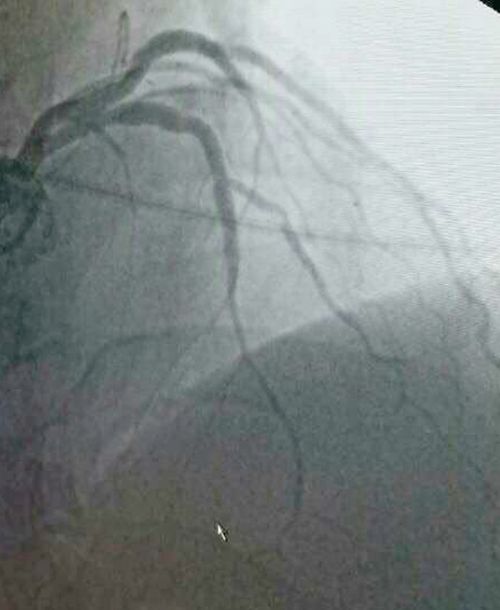

CRT-D植入术后,蔡文平主任又为一名冠脉支架植入术后患者进行了冠脉造影复诊,并指导科室医护人员为另一例放置双腔起搏器的患者进行了起搏器定期程控。陇南市第一人民医院心内科二病区自成立以来,在蔡文平主任的带领下,全体医护人员团结奋进、迎头赶上,不断学习先进的医学技术,在心血管介入治疗、电生理起搏治疗以及后期患者的复诊管理上逐步实现精准化、常态化、规范化,进一步缩小了与省内及周边发达地区同行之间的差距。

冠脉造影术中